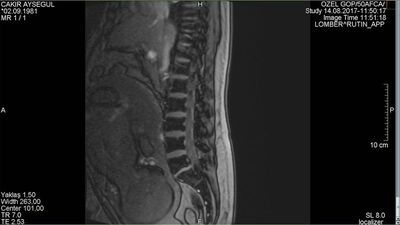

Bel fıtığı patlamış şekilde başvuran hastanın operasyonunu gerçekleştiren Doç. Dr. Karatay hastanın durumu ile ilgili şunları söyledi: "Hastamız 36 yaşında, 8 aylık hamile bir kadın. Bel ağrısı şikayetleri var. Gebelik öncesinde de bel fıtığı başlangıç tanısı koyulmuş. Gebelerde yüzde 50 oranında zaten bel ağrısı görüyoruz. Şiddetli bel ağrısı daha sonra ilerleyici semptomatik dediğimiz bel fıtığı noktasına gitmesi genellikle nadir görülür ama bu hastamızda sonucu güzel oldu. Ameliyatlık bir bel fıtığı olduğu için bize başvurdu. Hikayesinde istirahat ettiği, ilaç tedavisi gördüğü ama şikayetlerinin düzelmediğini anladık. Yaptırdığımız MR tetkikinde halk arasında patlamış dediğimiz ilerleyici bir bel fıtığı saptamamız üzerine kadın doğum ve anestezi hekim arkadaşlarımızla görüşerek hastamızın ameliyatını gerçekleştirdik. Ameliyatımız gayet başarılı geçti. Genel anestezi ile yapıldı. Özel bir cerrahi pozisyonda yapıldı. Anestezi açısından bebeğe hiç zarar verilmeyecek şekilde hızlı bir cerrahi ile ameliyatımız sonlandırıldı. Ameliyat sonrasında hastamız ilk defa güzel bir uyku uyuduğunu ifade ederek bir gece yattıktan sonra taburcu oldu."